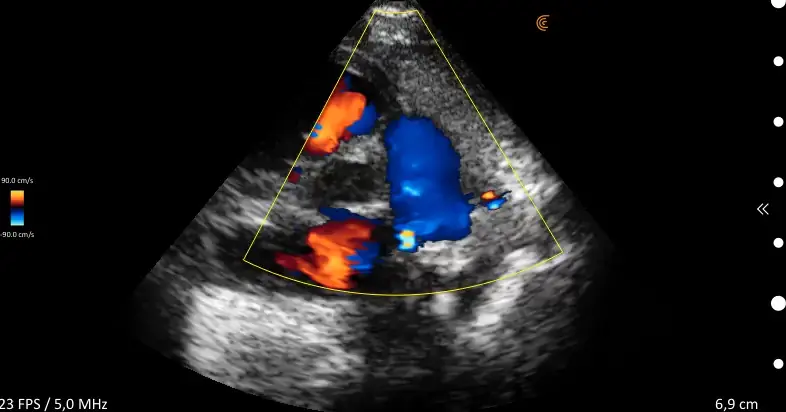

ProbeFix Dynamic is a new device that enables high-quality ultrasound measurements during dynamic exercise by keeping an ultrasound probe in place, allowing for muscle monitoring during intense movement and creating new research possibilities in muscle imaging.